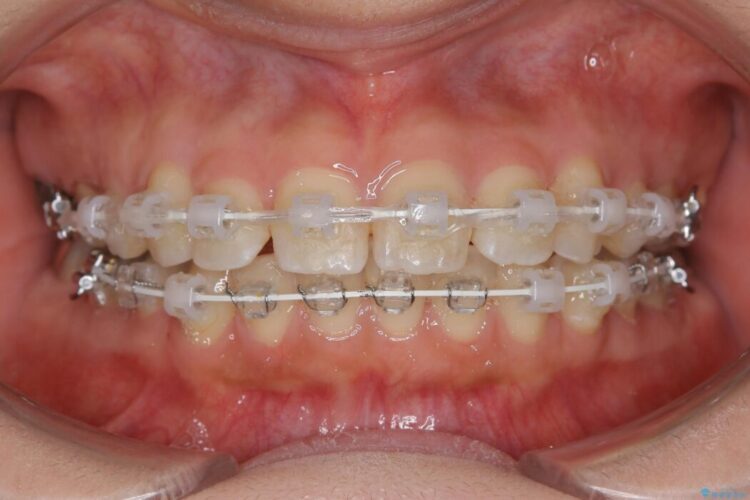

いつもでしたらマウスピース矯正をおすすめするのですが、自己管理の煩わしさから、目立たないワイヤー装置にて矯正治療を行うこととしました。

後戻りの程度としては軽度なので、治療期間としては短く終えることが出来ました。

前歯の正中線も改善され大変満足していただきました。